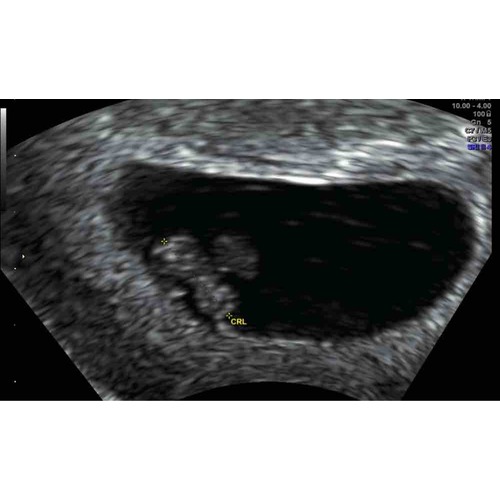

7+4🥰